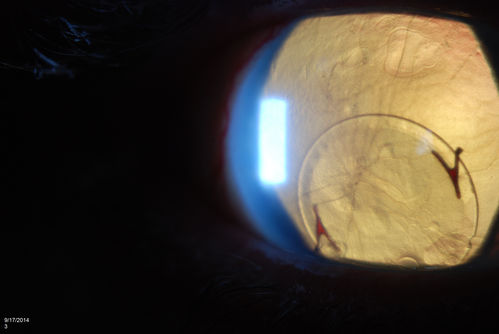

Free Floating Dislocated Lens in Vitreous

Patient comes in aphakic with dislocated lens floating to the back of the eye when laying down. Lens is laying up against the endothelium of the cornea when patient is right side up..